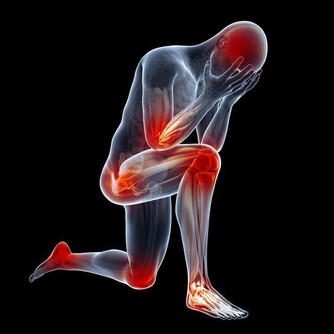

由於其在不同身體過程中的多種用途,當缺乏這種維生素時,人們肯定會遭受痛苦。對於孕婦來說,維生素B12水平低可能意味著神經管缺陷的風險增加。對於其他人,他們可能有患2型糖尿病和其他健康問題的風險。